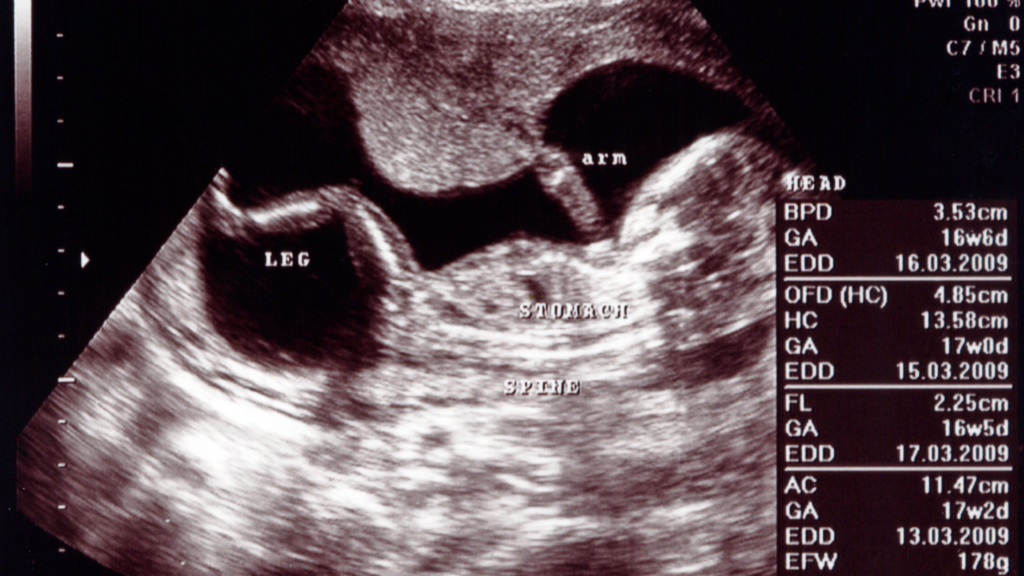

- 17 weeks pregnant: ultrasound – Get ready for your 20-week scan. It’s coming up very soon. Will you find out your baby’s gender? Find out at your local hospital whether you need to attend the scan by yourself or if your partner is able to come with you

Here are some pictures of what it looks like to be 17 weeks pregnant: